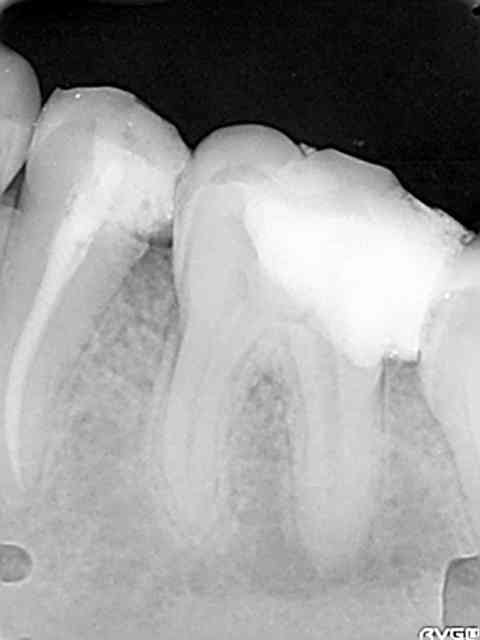

Une petite de ce matin et une plus ancienne, toutes les deux avec la même "recette".

Vous remarquerez en zoomant sur celle de ce matin comme le matériau a bien "squirté" en mésial. Devant de tels résultats, je ne vois pas pourquoi j'irai m'emmerder avec un system B...

Cematin yrjkt7 - Eugenol

Plusvieux swdvep - Eugenol